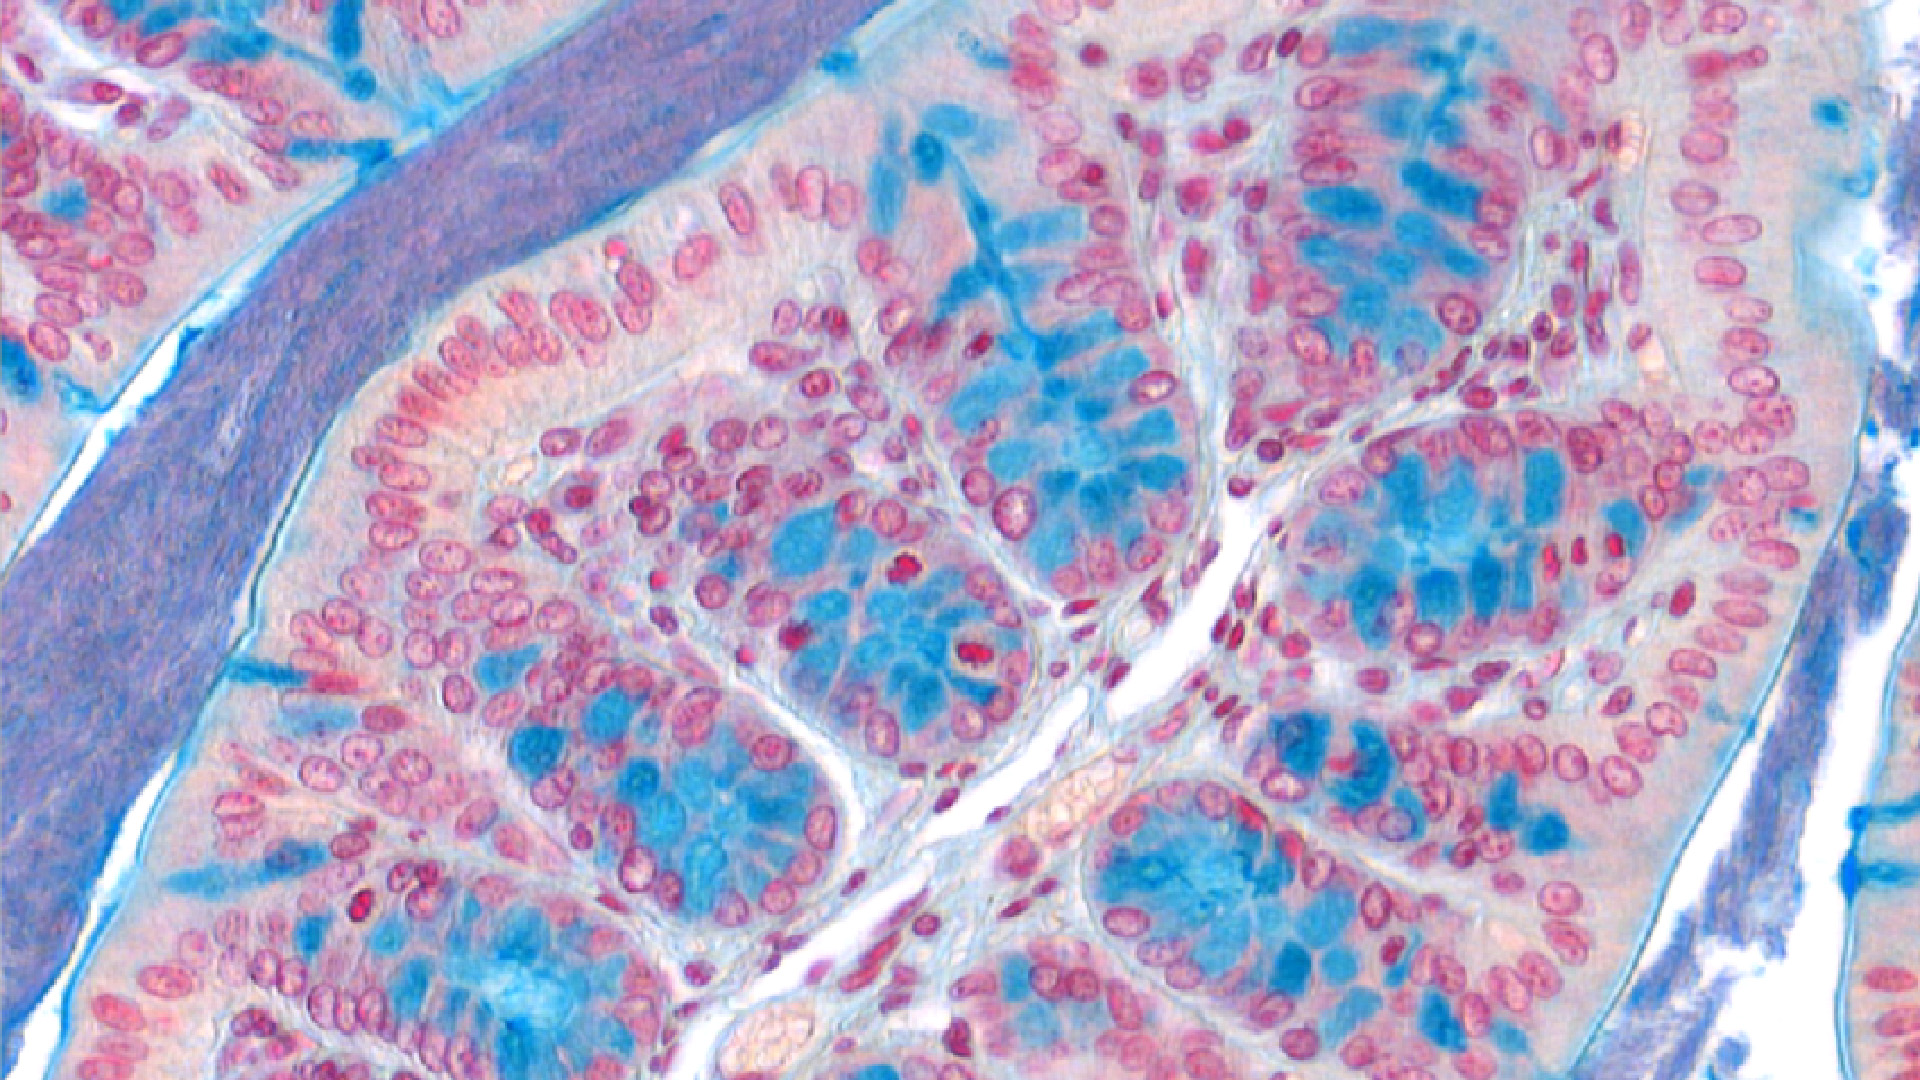

© Noëmie Daniel/Inserm

De précédents travaux menés par l’équipe de Benoît Chassaing, chercheur Inserm à l’Institut Cochin (Inserm/CNRS/Université Paris Cité), ont montré que la consommation de certains agents émulsifiants entraînait l’altération du microbiote intestinal[1] et son interaction avec l’appareil digestif. Ces altérations du microbiote conduisent à une inflammation intestinale chronique et à des dérégulations métaboliques. Plus précisément, ces recherches ont montré que la consommation d’émulsifiants alimentaires induisait la capacité de certains éléments du microbiote à rentrer en contact étroit avec l’épithélium – la première ligne de défense de l’appareil digestif qui normalement est stérile.

Dans cette nouvelle étude, les chercheurs ont voulu contrecarrer les effets délétères induits par la consommation d’émulsifiants en fortifiant l’épithélium intestinal. Pour cela, ils se sont intéressés plus spécifiquement à la bactérie Akkermansia muciniphila, qui, naturellement présente dans l’intestin, a déjà révélé avoir un impact sur les interactions du microbiote avec le reste de l’organisme. Par ailleurs, on sait que la quantité de cette bactérie se retrouve diminuée suite à la consommation d’agents émulsifiants. Des groupes de souris ont ainsi reçu des agents émulsifiants par le biais de leur alimentation, supplémentée ou non avec une dose quotidienne d’Akkermansia muciniphila. Les scientifiques ont observé que, tandis que la consommation d’agents émulsifiants alimentaires était suffisante pour induire une inflammation chronique associée à des altérations du métabolisme et à une hyperglycémie, les souris recevant Akkermansia muciniphila étaient totalement protégées contre de tels effets. L’administration d’Akkermansia muciniphila a aussi été suffisante pour prévenir l’ensemble des altérations moléculaires normalement induites par la consommation d’agents émulsifiants, et notamment le rapprochement des bactéries de la paroi de l’épithélium. « Ce travail conforte la notion que l’utilisation d’Akkermansia muciniphila en tant que probiotique pourrait être une approche pour maintenir la santé métabolique et intestinale contre les stress modernes tels que les agents émulsifiants qui promeuvent l’inflammation intestinale chronique, et les conséquences néfastes qui en résultent. De plus, cela suggère que la colonisation intestinale par Akkermansia muciniphila pourrait prédire la propension individuelle à développer des désordres intestinaux et métaboliques suivant la consommation d’émulsifiants : plus la présence de la bactérie est importante, plus l’individu serait protégé des effets néfastes des additifs alimentaires sur le microbiote », explique Benoît Chassaing, dernier auteur de l’étude.